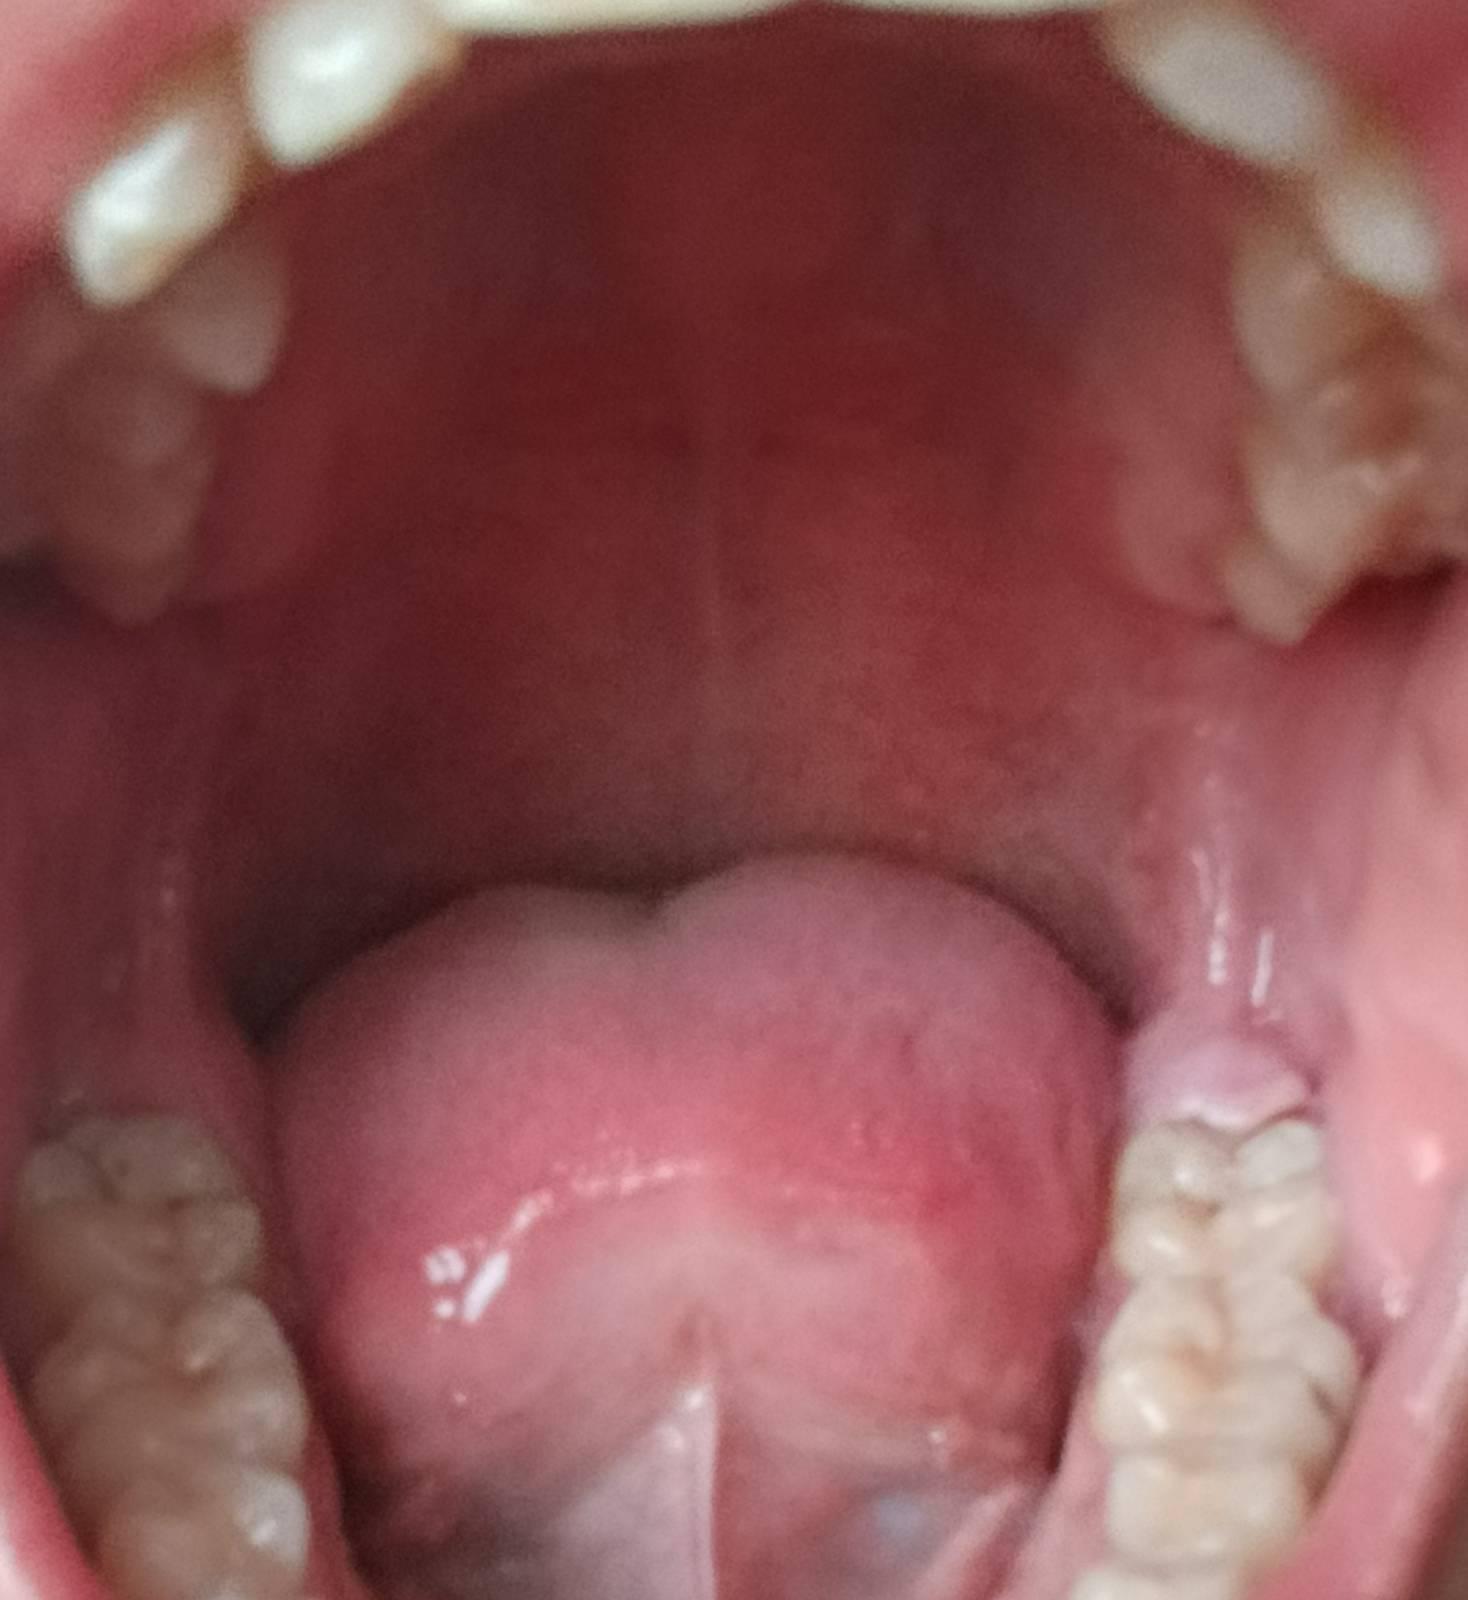

เหงือกเป็นแบบนี้คืออะไรครับ T-T

ตรงเหงือกด้านในสุดหลังฟันกรามของผม ตอนแรกมันเป็นตุ่มนิ่ม ๆ ครับ แล้วหลังจากนั้นมันก็บวมสูงขึ้นเรื่อย ๆ จนตอนนี้เหงือกตรงบริเวณนั้นมันยกตัวขึ้นและไม่ติดกับฟันแล้วครับ เป็นแค่ด้านขวาด้านเดียว ส่วนด้านซ้ายปกติครับ มันเป็นอันตรายหรือเปล่าครับ แล้วมันคืออะไร